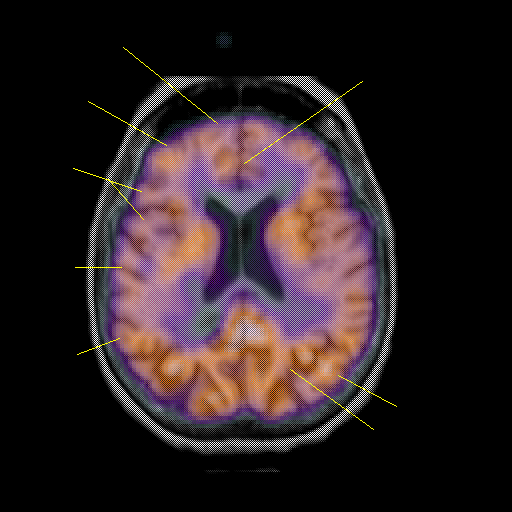

overlay: Slice 33

Slice 33

Unlabeled

Pointers

Labeled